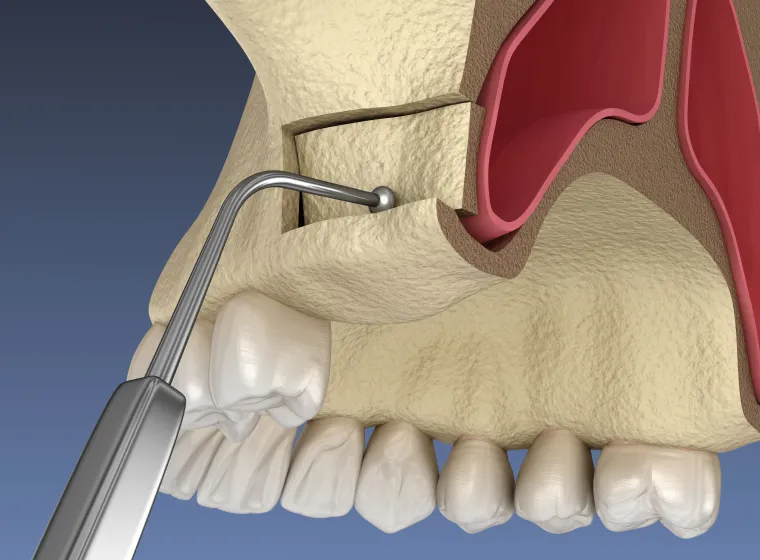

サイナスリフト(上顎洞挙上術)

上顎奥歯の骨が薄いケースで行う方法です。上顎洞と呼ばれる空洞の粘膜を持ち上げ、そこに骨補填材を入れて厚みを確保します。広い範囲で骨が足りない場合に有効です。

このほか、ソケットリフトやスプリットクレストなど、患者様ごとの状態に適した方法を選択します。骨造成は「骨が足りないからインプラントはできない」と言われた方にとって、新たな選択肢をもたらす技術です。